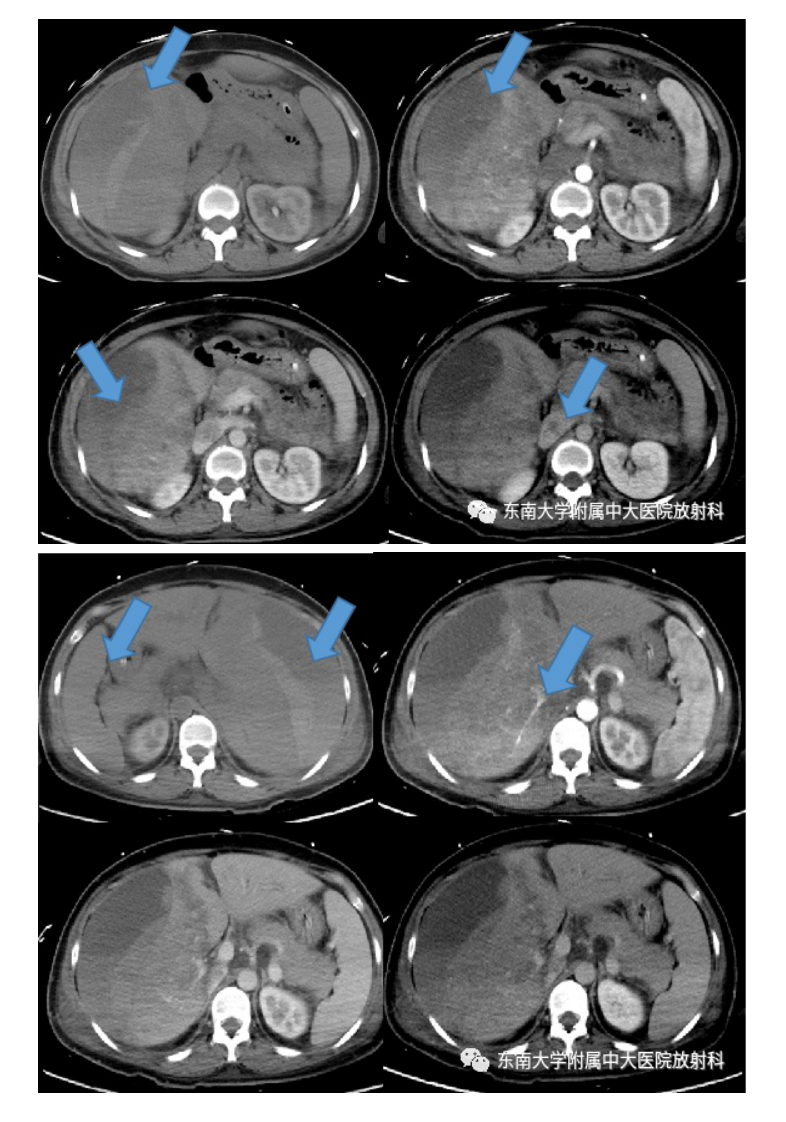

20210621_3【晨读结果公布】2021.06.21消化系统疾病——病例1HELLP;病例2:ANCA相关性血管炎;病例3:原发性肝癌.pdf